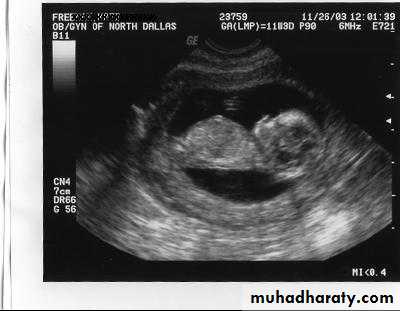

CRL Crown – rump length – 13 wk+6 daysBPD biparietal diameter, HC head circumference14 wk -20 wk